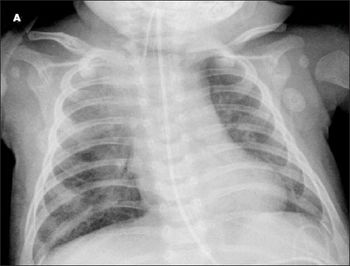

Acute bronchiolitis, COPD, giant bullous emphysema, hypersensitivity pneumonitis, and pulmonary tuberculosis may present diagnostic challenges.